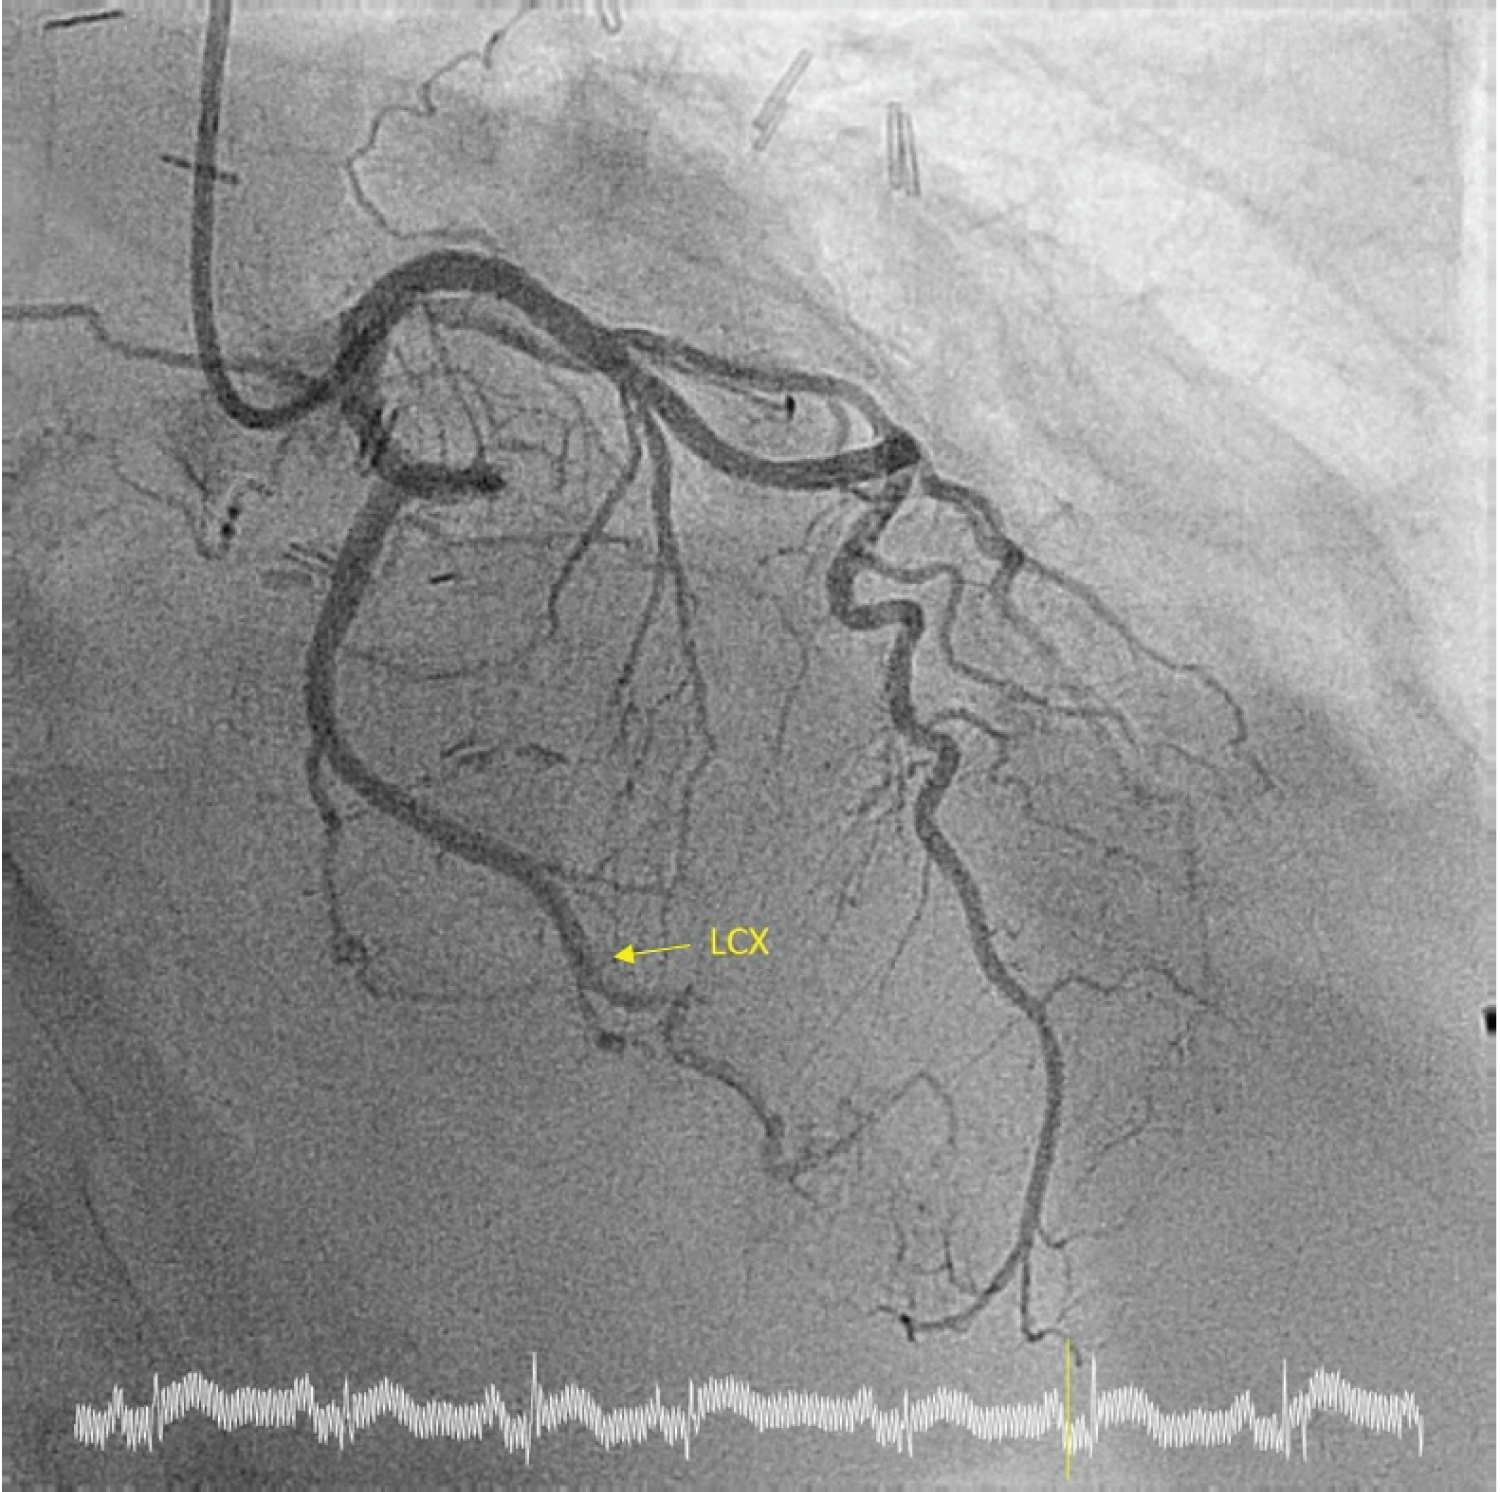

This case is about a 65-year-old man who was diagnosed of stage IV Thymic Carcinoma in 2012, with two recurrences in 2013 and 2015. He underwent a surgical treatment in 2012 with surgical excision of the mediastinal mass, right upper and medium lung lobe, and upper left lobe, pericardiectomy, excision of phrenic nerve, IVC, innominate left vein and portion of innominate right vein, followed by different radiation and chemotherapy. From 2018, the patient was CPAP addicted for respiratory failure. At the time of our meeting with the patient, an experimental protocol with Pembrolizumab was still in progress. He was admitted to emergency department in a cachectic status with worsening dyspnoea in the last few days. The Glasgow Coma Scale was 15/15; the blood pressure was 90/60 mmHg and the pulse rate 74 bpm. The auscultation was totally subverted with harsh lung sound, heart tones were difficult to hear. The biochemistry panel revealed TnT hs 35 ng/L, CRP 80 mg/L, creatinine 80 umol/L, GFR 90 ml/min/1.73 m2. He denied any chest pain, and he complained of dyspnoea and weakness. The ECG showed an ST-elevation in DI-aVL and V4-V6 suggesting an ACS (Figure 1), so the patient has been urgently transferred to hemodynamic units. An emergency coronary angiogram was performed, but the exam showed no significant coronary artery stenosis (Figure 2). The transthoracic echocardiography performed in the cath lab revealed a mass infiltrating the left ventricular myocardium with consequent akinesia of lateral and anterior wall without impairment of the right ventricle or valvular disease (Figure 3). For a better diagnostic picture, we performed a thoracic CT scan (Figure 4). The exam revealed a mass of 17*10*12 cm without a cleavage plan from the LV, which infiltrated the myocardium surrounding the left circumflex coronary artery. This finding was interpreted as the cause of the ST-elevation.

Figure 2: Coronary Angiogram: Absence of significant coronary artery stenosis. View Figure 2